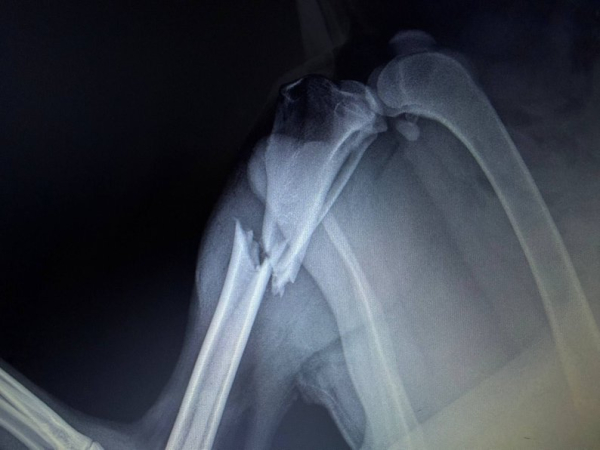

Песик молодий, менше двох років. У нього діагностували перелом гомілки задньої лапи. Провели термінову операцію — вона пройшла успішно, лапка заживає, тварина поступово відновлюється.